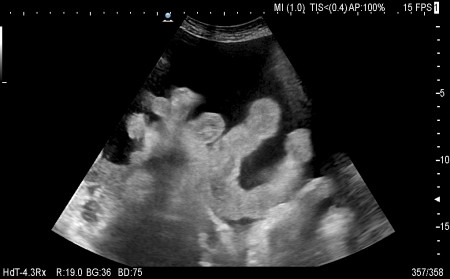

Реальный асцит

phpBB [video]